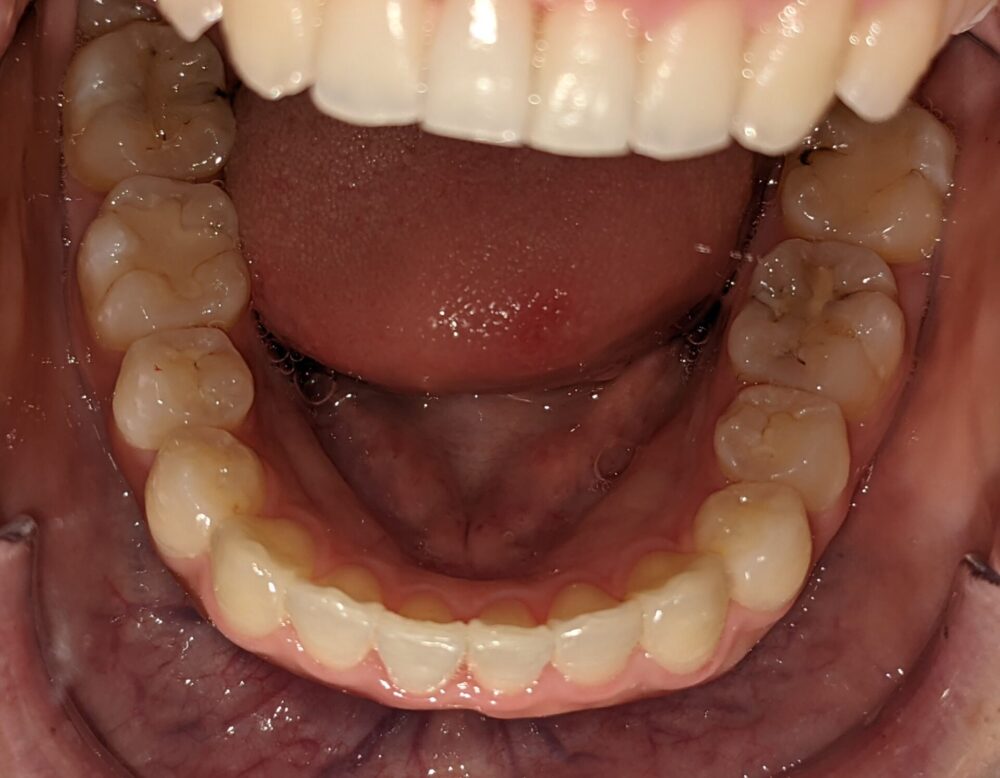

- 主訴

- 前歯が気になる(上下)

- 診断名あるいは主な症状

- 叢生

- 年齢

- 22才

- 治療に用いた主な装置

- マウスピース

- 抜歯部位/抜歯有無

- 無し

- 治療期間

- 約半年

- 総費用

- ¥840,000

- 主なリスク・副作用

- 歯肉退縮,歯根吸収,疼痛,咬合の違和感,装置の違和感,虫歯,歯肉炎